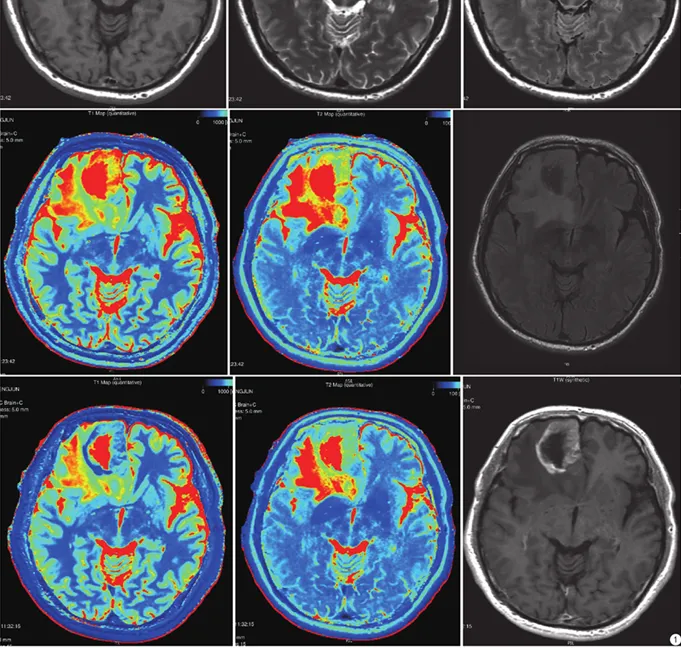

2、强化表现:增强扫描反映的是血脑屏障是否存在或完整,病变的强化程度与血供及血脑屏障密切相关。低级别胶质瘤血脑屏障功能接近正常(不强化),高级别胶质瘤血脑屏障功能缺乏(强化、肿瘤破坏血管导致血脑屏障形成异常以及肿瘤新生血管),大多数胶质瘤的恶性程度越高,其血脑屏障受损越重,强化就越明显。

高级别胶质瘤。从左至右、从上到下分别是:合成图像(T1WI、T2WI、T2 FLAIR);合成T1 mapping、合成T2 mapping、常规扫描T2 FLAIR;增强后合成图像(T1 mapping+C、T2 mapping+C、T1WI+C)

低级别胶质瘤。从左至右、从上到下分别是:合成图像(T1WI、T2WI、T2FLAIR);合成T1 mapping、合成T2 mapping、常规扫描T2 FLAIR;增强后合成图像(T1 mapping+C、T2 mapping+C、T1WI+C)